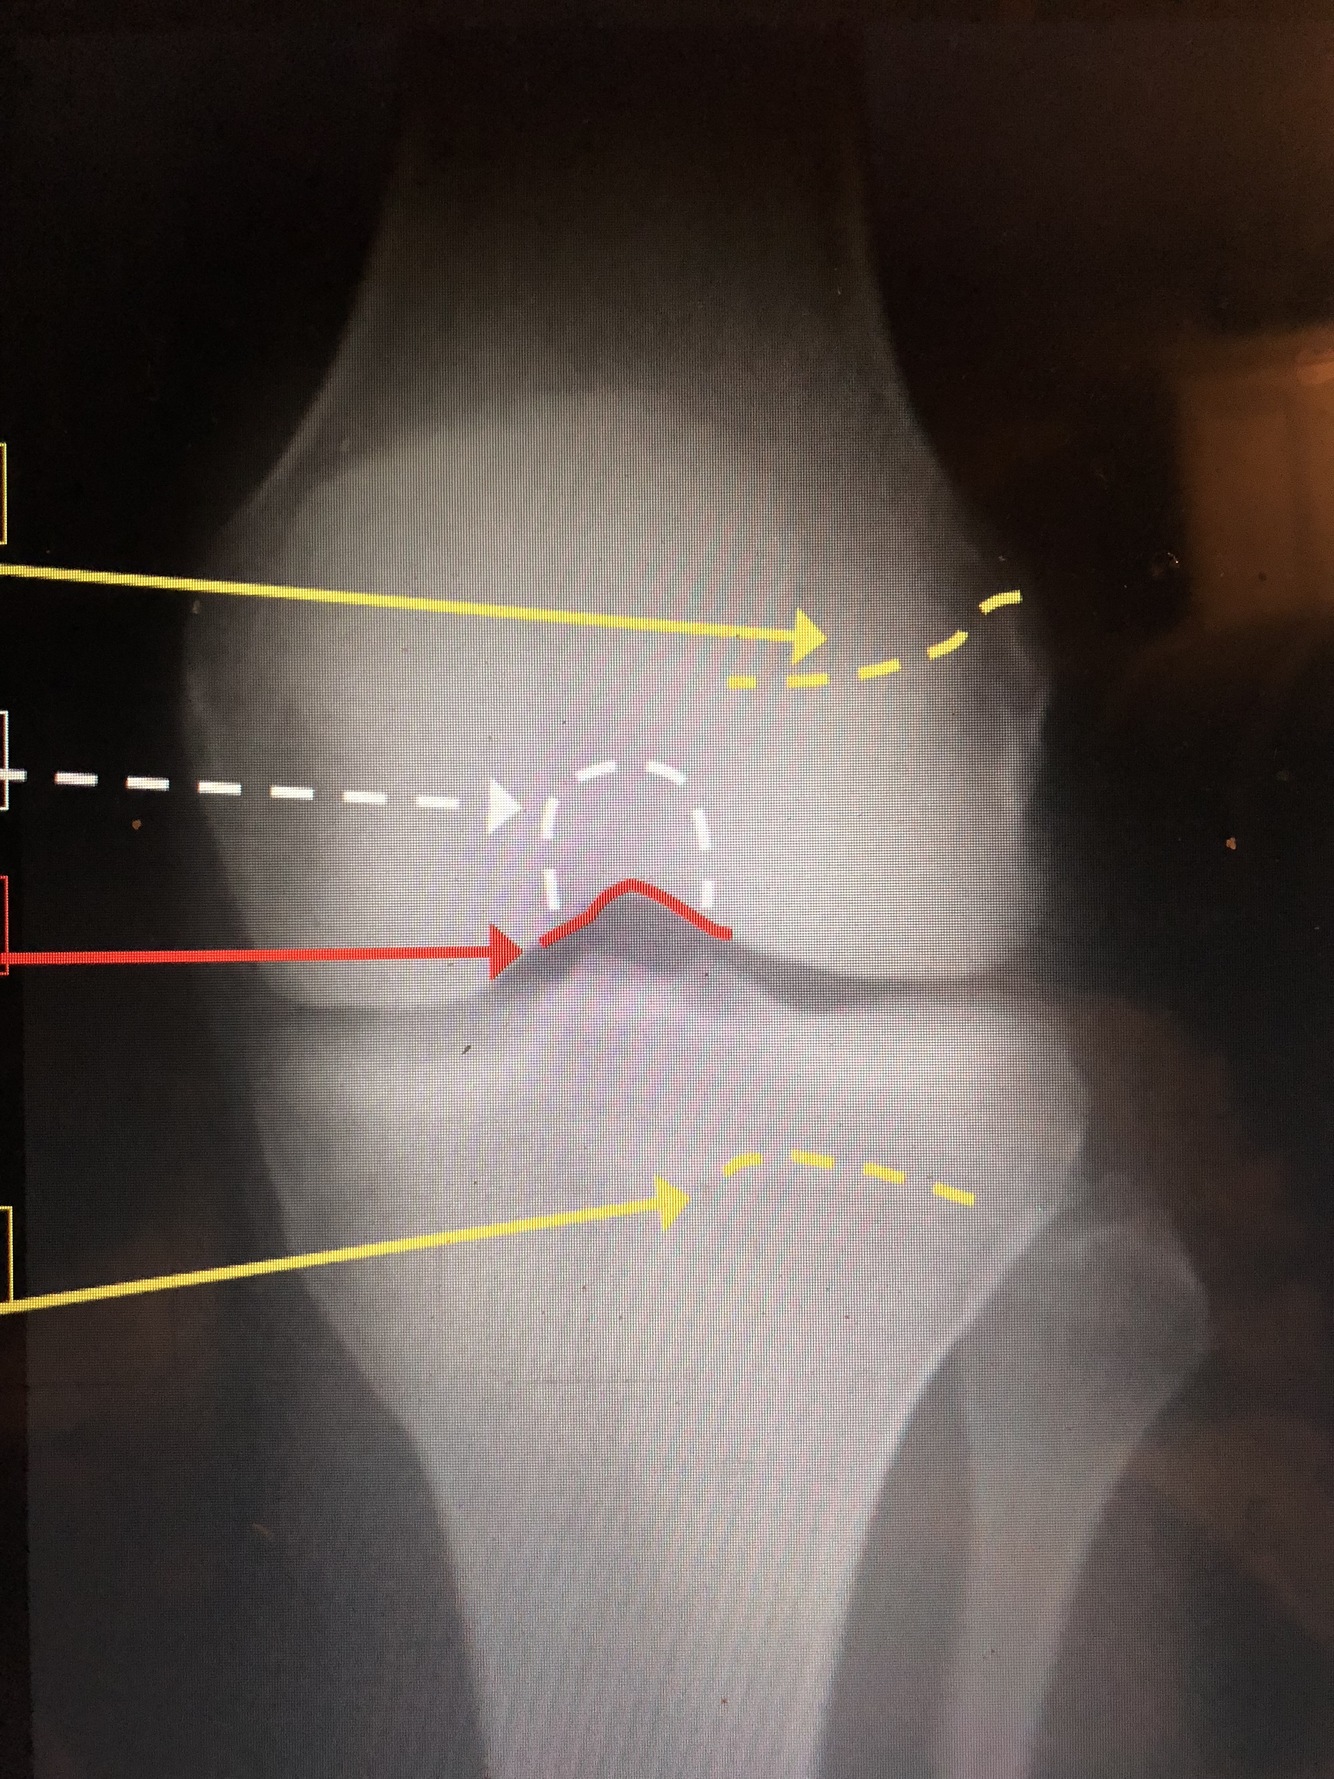

What is the top yellow dotted line?

Femoral Physeal Scar

What is the bottom yellow dotted line?

Tibial Physeal Scar

What is the white dotted line?

Intercondylar Fossa

What is the red line?

Intercondylar Notch

What is the white line?

Popliteal Surface of the Femur